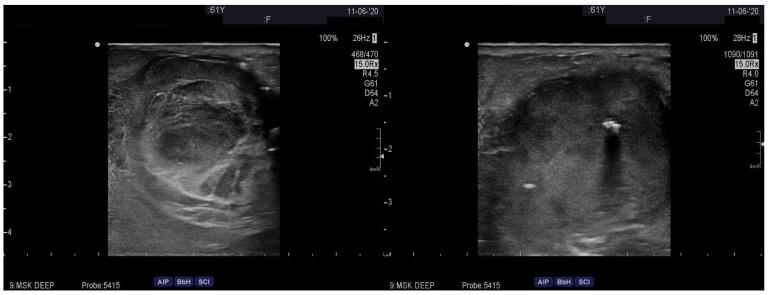

肝移植患者中快速生长并破裂的大隐静脉动脉瘤。

Rapidly Growing and Ruptured Great Saphenous Vein Aneurysm in a Liver Transplant Patient.

Venous aneurysms are rare vascular malformations that can lead to significant clinical complications, including thrombosis, pulmonary embolism, rupture, and even fatal outcomes when not promptly and adequately managed. This case report presents a liver transplant patient under immunosuppressive therapy who developed a rapidly progressing great saphenous vein aneurysm, ultimately requiring urgent surgical intervention due to acute bleeding from the ruptured aneurysm. Immunosuppression emerges as a potential key factor in the formation and rapid growth of the aneurysm, with the pathophysiological mechanism potentially involving increased expression of specific matrix metalloproteinases. Further research is warranted to gain a better understanding of the role of immunosuppression in the development of venous aneurysms.

摘要

静脉瘤是一种罕见的血管畸形,如果不能及时、充分地治疗,可能会导致严重的临床并发症,包括血栓形成、肺栓塞、破裂,甚至导致致命后果。本病例报告介绍了一位接受免疫抑制治疗的肝移植患者,他出现了迅速进展的大隐静脉瘤,最终由于破裂的动脉瘤急性出血,需要紧急手术干预。免疫抑制被认为是动脉瘤形成和快速生长的一个潜在关键因素,其病理生理学机制可能涉及特定基质金属蛋白酶表达增加。需要进一步的研究来更好地了解免疫抑制在静脉瘤形成中的作用。